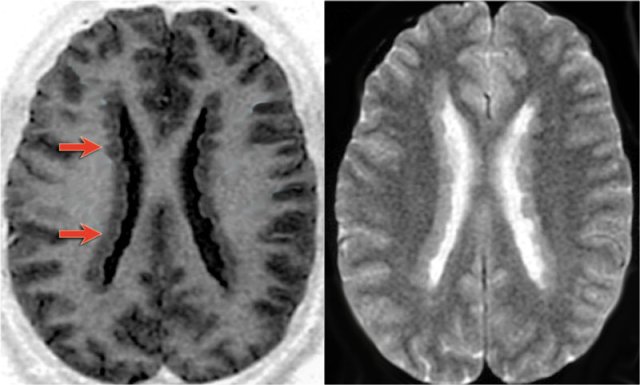

The images show mesial temporal sclerosis with a hyperintense and shrunken hippocampus (red arrows), and secondary enlargement of the left temporal horn of the left laterale ventricle.

Also notice associated subcortical hyperintensity in the left temporal lobe indicating focal cortical dysplasia.

35-year-old patient with refractory temporal lobe epilepsy.

MR shows subtle hyperintensity of the left hippocampus on the axial FLAIR (blue arrow) and atrophy of the left hippocampus on coronal images (yellow arrow).

The patient was succesfully treated with amygdalo-hippocampectomy on the left.

Axial FLAIR, axial DWI and coronal T2WI demonstrate a hyperintense hippocampus with a slightly compressed temporal horn of the lateral ventricle consistent with hippocampal edema.

DWI shows diffusion restriction due to cytotoxic edema in the acute stage of the status epilepticus.